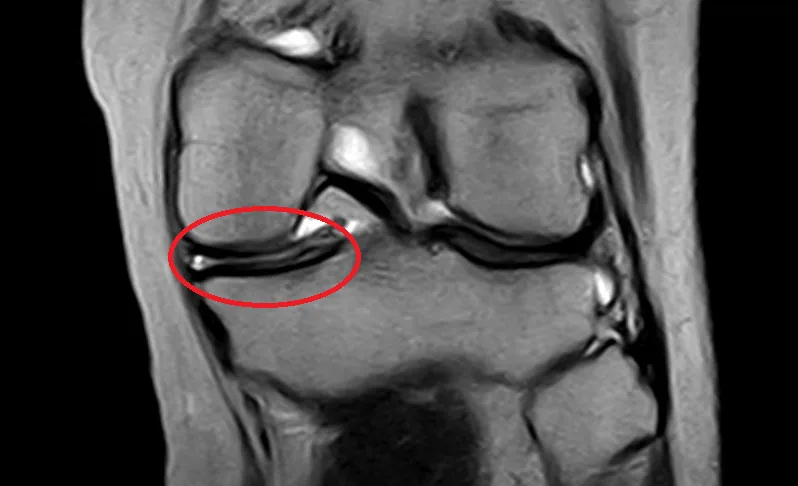

半月板損傷

Meniscus Tear